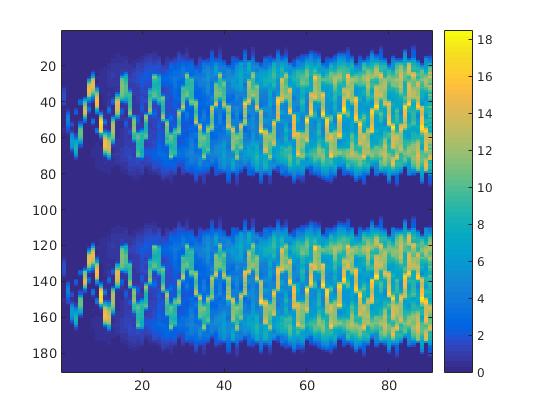

To simulate the synthesized SPECT data, we apply a Radon transform assuming a double detector gamma camera, which counts photons from two opposing projection angles per time step. For the more simple data set, we let the camera rotate clockwise around two degree per time step, in case of the complex data set we used modified projection angles, i.e. the camera alternatingly projects from an angle of i and 45+i degrees, in order to simplify the reconstruction. Each collimator consists of detector bins, so we obtain data points per time step and projection angle. The resulting sinogram data of the two underlying data sets are shown in figure 3.

In a first test, every image sequence was reconstructed out of the exact given sinograms. Additionally we tested noise corrupted data by first scaling the sinogram by a parameter , corrupting them with Poisson noise via the MATLAB imaging toolbox command imnoise and finally rescaling the image to the original range (see figure 4). The average count number per time step (i.e. the average of the discrete -norm of the data at each time step) is approximately in case of the heart-shaped data set and ca. in case of the rat liver simulation. The results at a certain number of time steps can be seen in figure 6 and 7. For comparison, we additionally performed a reconstruction with a simple alternating EM method, keeping the assumption that the tracer can be modelled as a sum of indicator functions and subconcentration curves, but neglecting any regularization terms. In all tests, the outer iteration number was set to 1000 with 10000 inner iterations per subproblem, to obtain a result within a reasonable time period. As stopping criterion, we chose the primal dual residual (cp. [12]) for the inner and the maximum over the Frobenius norms of and for the outer iterations. The results are displayed in 6 and 7 respectively.

As one can see in both figures, the reconstruction method applied to each data set performs very well, especially in contrast to the simple alternating EM method. This clearly shows the benefits of the proposed regularization methods. In case of noise-free given data, the shape of every object, where especially the heart is of higher interest, is clearly defined. As expected, we often observe errors in the edges of each region and where two regions are directly connected (the heart and the upper left circle). This causes the algorithm to incorrectly assign these pixels to another region. Furthermore, the reconstruction difficulties increase with an increase in noise. Some more pixels are assigned to the wrong region, which leads to a small hole-like structure within the heart region and causes a slight blurring effect. In the second data set the method clearly outperforms several other approaches by providing very clearly defined regions and even reconstructing fine structures of the phantom. However, as mentioned before, a clear reconstruction of the rat liver required highly optimized parameter sets, which makes the whole problem quite susceptible to parameter changes.